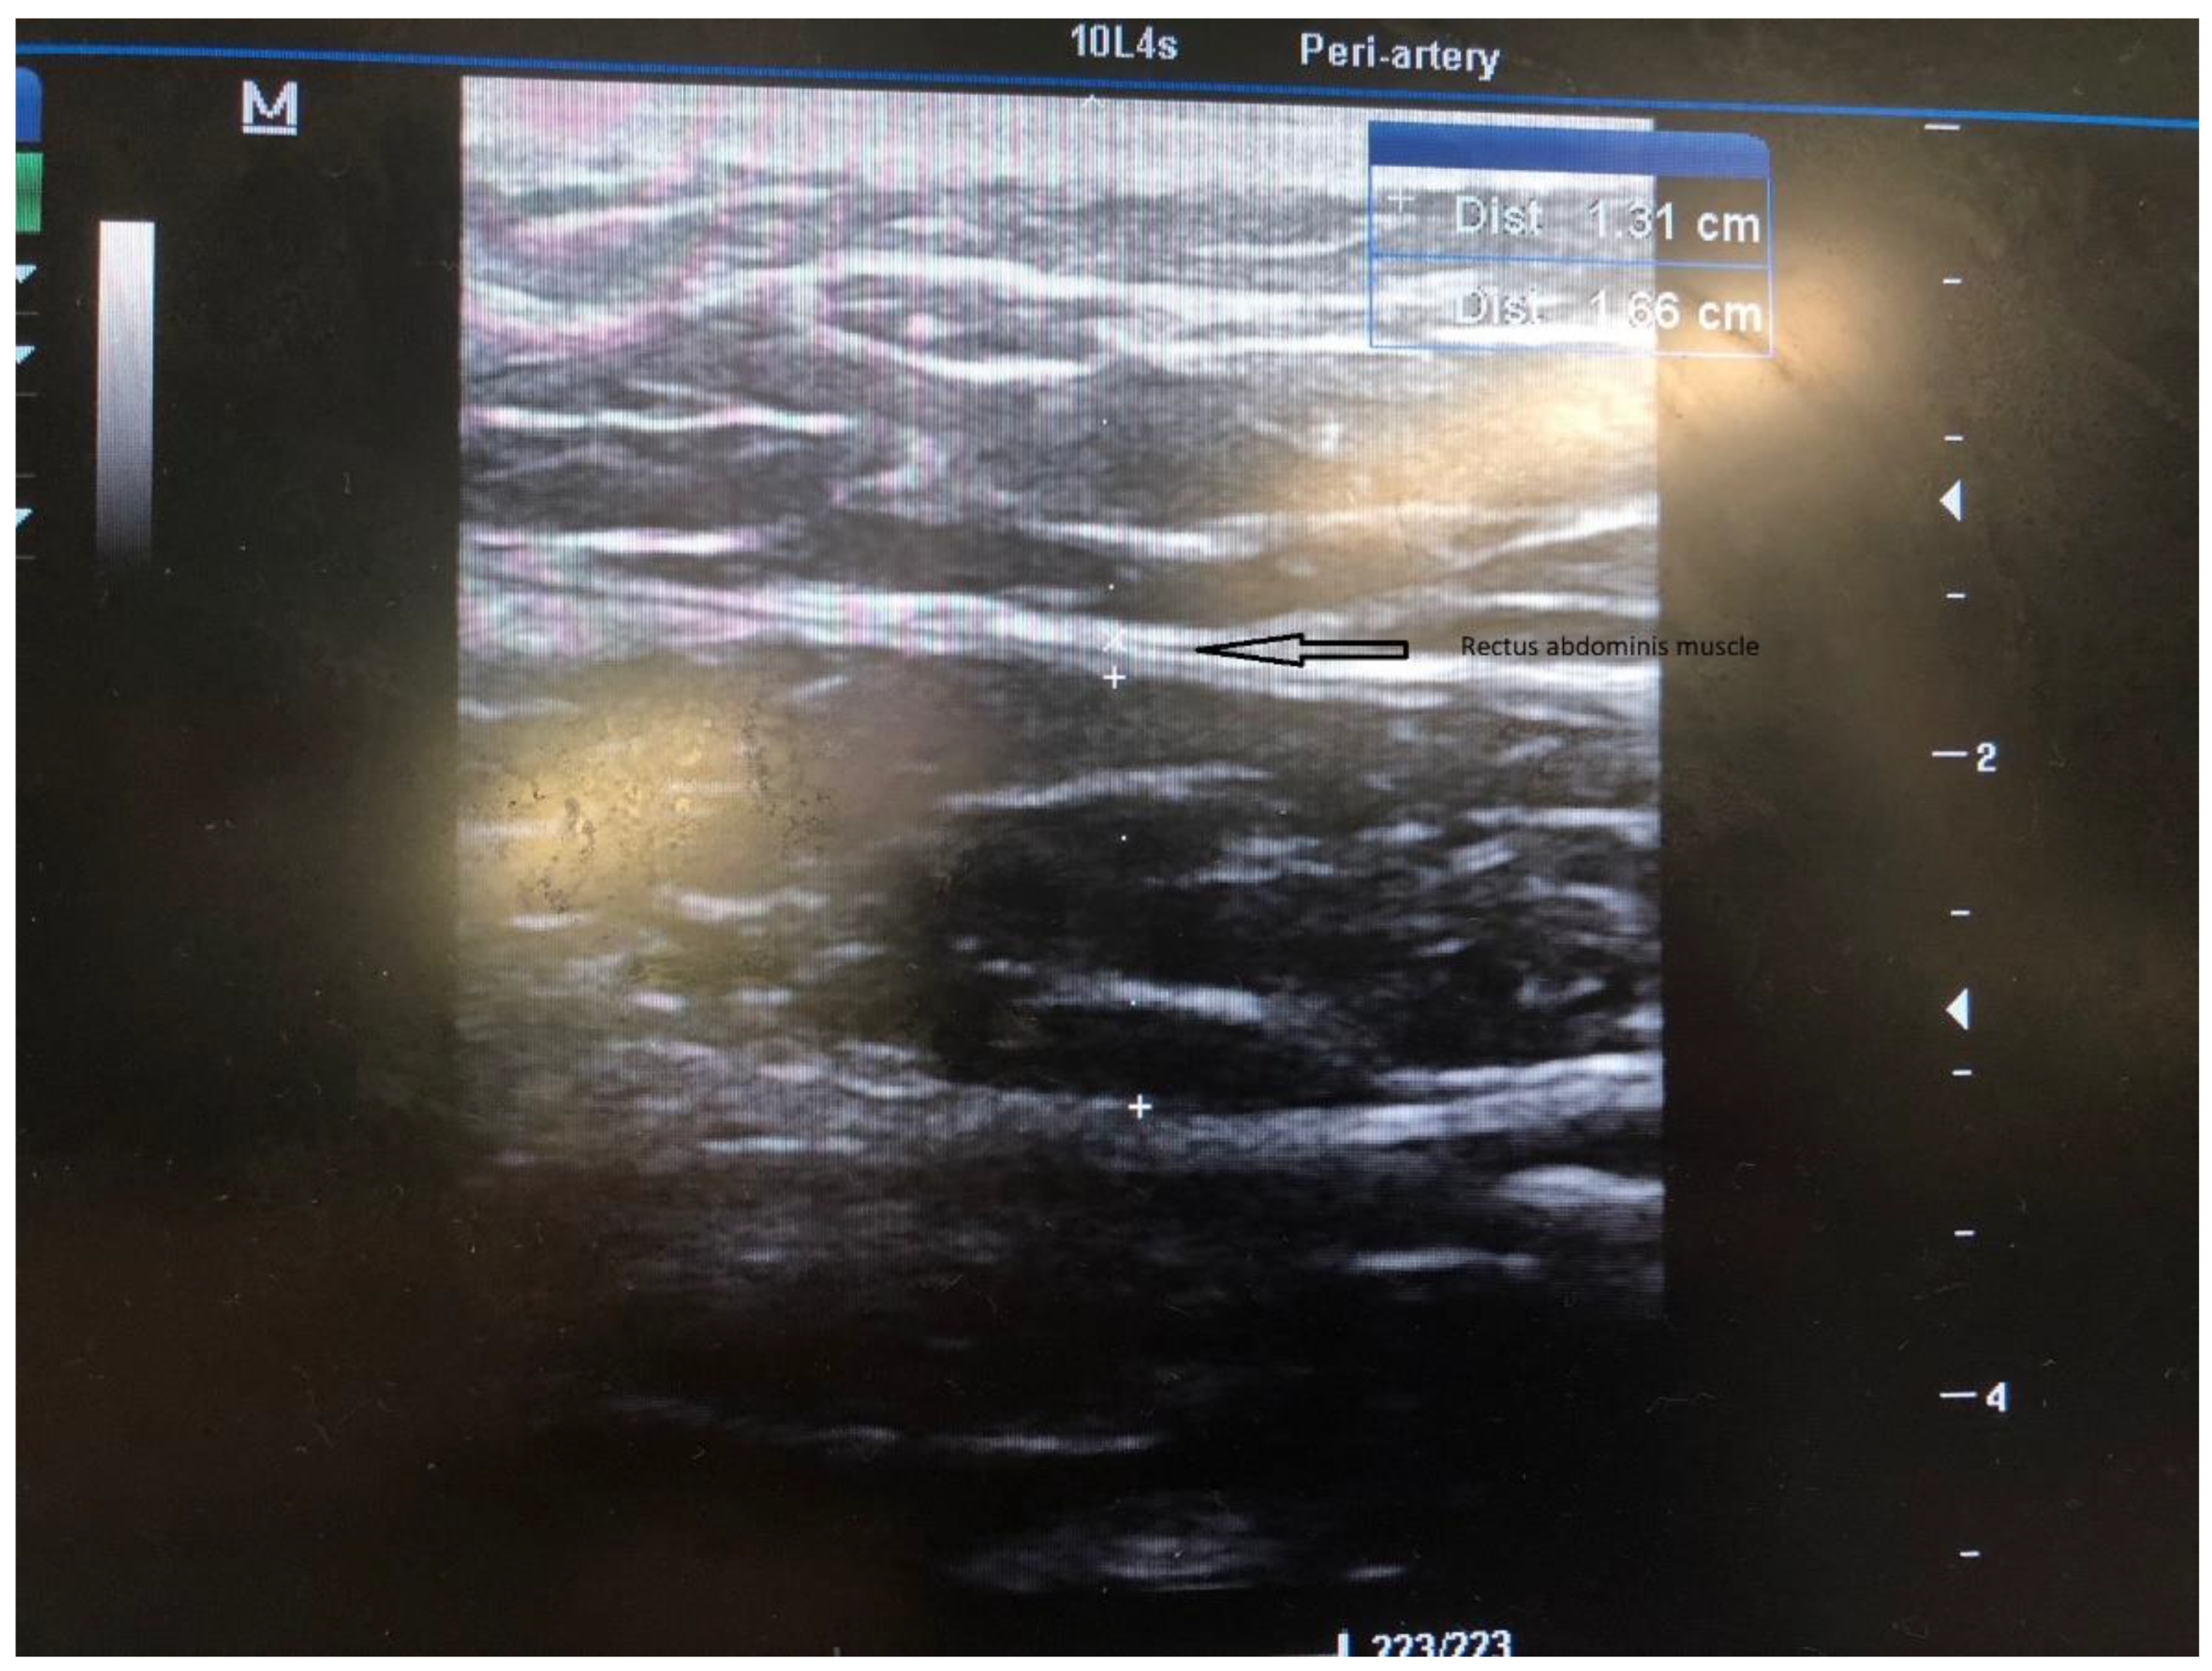

Figure 2.

US evaluation and measurement of the rectus abdominis muscle.

In all candidates for peritoneal dialysis (PD), a laparoscopic insertion of PDC under general anesthesia has been performed in our institution for the past 15 years. Recently, we implemented a modified technique with intraoperative US evaluation of the abdominal wall on the side of PDC insertion. The abdominal surgeon performs all PDC insertions under general anesthesia, while the nephrologist joins the surgery to perform an US of the abdominal wall. The side of PDC is agreed upon with patients preoperatively after obtaining informed consent. The patient is placed supine, and a single preoperative antibiotic prophylaxis with 1 g to 2 g cefazolin is given 30 min before the skin incision. If a penicillin allergy is known, patients get 500 mg of vancomycin. The sterile operative field is prepared per standard protocol. Thereafter, the position of the internal cuff and a skin exit site are marked. The coiled Tenckhoff catheters with two dacron cuffs and a special trocar are used for rectus sheath tunneling. When the procedure is commenced, an US evaluation of the abdominal wall is performed ipsilaterally to the PDS insertion into the abdominal cavity. (Figure 1). The rectus abdominis muscle width is measured with the US (Figure 2), and the course of the inferior epigastric artery is determined with colored US Doppler (Figure 3). On the abdominal wall, the thickest part of the rectus abdominis muscle and the course of the inferior epigastric artery are both marked with a pencil (Figure 4). After that, the position of the internal cuff is determined 2–3 cm laterally from the umbilicus, where the rectus muscle is sufficiently thick. The positions of the external cuff and the skin exit site are also marked on the skin before insertion. After the US evaluation of the abdominal wall is completed, the laparoscopic insertion of PDC is performed. A standard laparoscopy is performed with one 5 mm trocar above the umbilicus and a 5 mm 30-degree camera. The second 5 mm trocar is inserted laterally as a working trocar for a laparoscopic grasper. The 5 mm skin incision is initially performed above the umbilicus, and a Veress needle is blindly introduced into the abdominal cavity. Aspiration and a water drop test is performed to ensure that the Veress needle is properly inside the peritoneal cavity. Pneumoperitoneum is created with CO2, and the intraabdominal pressure is maintained around 12 mm Hg, as in standard laparoscopy. A 5 mm trocar is blindly introduced into the abdominal cavity at this site. Although all patients have preoperative abdominal US performed, we further perform diagnostic laparoscopy with a 5 mm 30-degree camera to exclude any other associated intraabdominal pathology. Contralateral to the PDC insertion, another 5 mm trocar is inserted under laparoscopic vision and a camera is moved to that trocar so that the entry site of the catheter into the peritoneal cavity can be visualized during insertion. The patient is tilted to a slight Trendelenburg position, thus allowing a better exposure of the deep pelvis, which is the point for inserting the PDC tip. The Trendelenburg position enables the small bowel loops to retreat from the pelvis so that the pelvis can be further inspected for possible adhesion. The advantage of laparoscopy is also to enable advanced laparoscopic procedures, such as adhesiolysis if needed. Thereafter, the 1 cm skin incision is performed ipsilateral to the side of PDC placement, and a special trocar is used for rectus sheath tunneling. Because of the preoperative US evaluation of the abdominal wall, we are aware of the inferior epigastric artery course, so we can accommodate the rectus sheath tunneling course so as to avoid vessel injury and bleeding. Rectus sheath tunneling is performed with a special trocar, through which the PDC is then inserted into the abdominal cavity. The trocar is introduced under a 45-degree angle through a small skin incision into the subcutaneous tissue and is then blindly forwarded through the abdominal wall (Figure 5 and Figure 6). The peritoneum is penetrated under direct laparoscopic vision to avoid any bowel or large vessel injury. The PDC is introduced through the trocar into the abdominal cavity, and the trocar is removed. With an atraumatic laparoscopic grasper, the coiled tip of the PDC is placed into the deep pelvis and the inner cuff is placed preperitoneally under direct laparoscopic supervision. The PDC is exteriorized laterally, and the outer cuff is placed in the subcutaneous tissue. The distance between the outer cuff and the skin exit site should be 2–4 cm. At the end of the laparoscopy, the proper position of the PDC tip and potential bleeding from the peritoneum at the trocar and PDC breakthrough sites are rechecked, respectively. All trocars and working instruments are removed from the abdominal cavity, and the pneumoperitoneum is released. The PDC is flushed with 50 mL of normal sterile saline to ensure the fluid flows freely in and out of the abdominal cavity. The fascia at trocar sites is sutured, and skin incisions are sutured with 4/0 absorbable sutures. The latter are infiltrated with a local anesthetic. When the surgical part of the PDC insertion is completed, an US is performed again to check for a proper position of the PDC tip and inner cuff. The outer end of the PDC is connected to the titanium adapter and transfer set. The complete outer part of the PDC is covered with gauze and transparent dressing. Following the procedure, the patient is admitted to the nephrology department, where a small volume flushing (200–500 mL) is started the next day. According to our institutional protocol, after laparoscopic insertion of the PDC, all patients have to wait 4–6 weeks before a full PD is commenced to achieve full healing of both the skin and abdominal wall wounds at trocar sites, thereby preventing (or minimizing) the possible leak. The patient is advised to avoid heavy lifting and strenuous physical activity for 4–6 weeks after the procedure.

In our experience, US guidance is of great benefit for correctly positioning the PDC into the abdominal wall. It allows us to determine the thickest part of the rectus abdominis muscle and the ideal site of the internal cuff position within the rectus sheath. In addition, the US-Doppler can help to identify the course of the inferior epigastric artery and its major branches and thus helps avoid major bleeding during surgery. After the PDC insertion, the US helps us to check the proper position of the internal cuff and to correct the position if necessary [7]. Although the laparoscopic technique is very effective and safe, it does not preclude complications during blind rectus sheath tunnelling. Hence, we opted to modify our previous technique to ensure the safest and most effective approach. Moreover, we noticed increased pericatheter dialysate fluid leaks in our last 40 patients. All these patients were evaluated with US, and in a few of them, we observed the internal cuff either displaced into the subcutaneous tissue or placed in a suboptimal place within a very thin rectus muscle. Besides the technical failure, other factors predispose to a pericatheter leak, such as a thin abdominal wall, bad tissue healing, and other patient conditions. Hence, we decided to optimize the technical aspect to perform the most optimal PDC insertion. We believe that the afore-described technique presents a step forward, and we see a great benefit of it in providing the most optimal PDC insertion while reducing the technical failure of PD. We believe that combining preoperative and intraoperative US evaluation of the abdominal wall with concurrent use of laparoscopy is the safest and most effective technique of PDC insertion. However, so far, we have performed the modified US-guided technique in only a few of our patients, and we do not have data on long-term results. Due to the small number of patients, at the moment, we cannot objectively evaluate the results and compare both techniques.